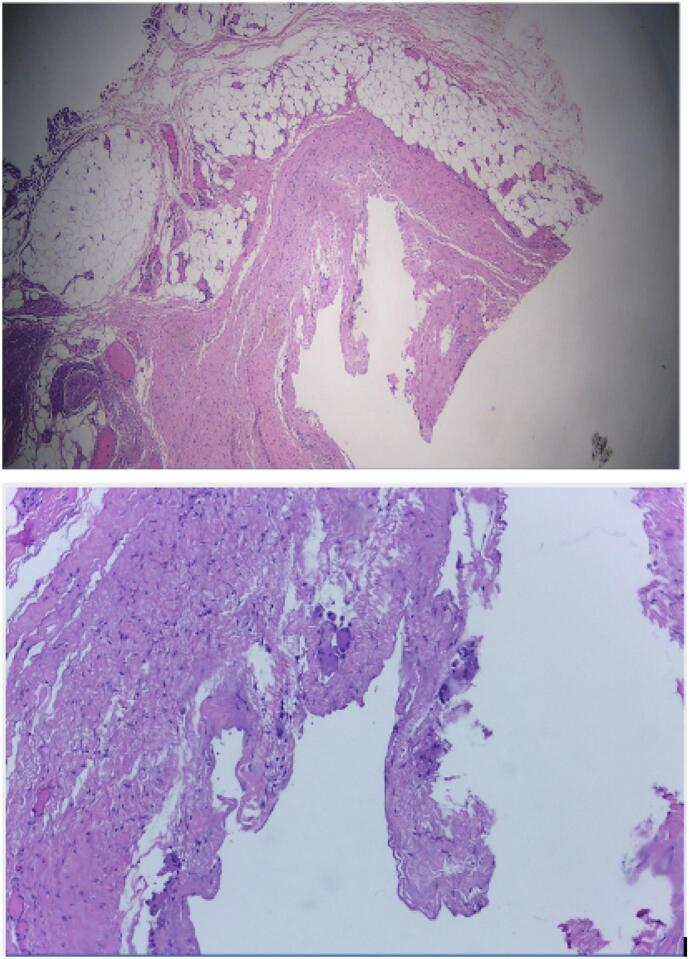

A male patient, 68 years old, came with complaint of a lump in the left cruris since one year ago. Nine months later, the lump has increased in size like a chicken egg and still felt painless. MRI result revealed a well-circumscribed multilocular cystic lesion in the peri-osseous soft tissue of the tibia. We performed directly excisional biopsy within the mass, and the histopathology result was periosteal ganglion cyst.

The exact pathogenesis of periosteal ganglion is unclear. Synovial herniation and mucoid degeneration of the connective tissue of the periosteum are two suggested mechanisms. In some cases, ganglion cysts may compress nearby nerves. Surgical treatment is recommended for patients who still experience symptoms after non-surgical management has failed. Complete resection of the cyst and surrounding periosteum is recommended to prevent recurrence. After 6 months post-operative follow up clinical examination, no recurrence symptoms founded on the patient.